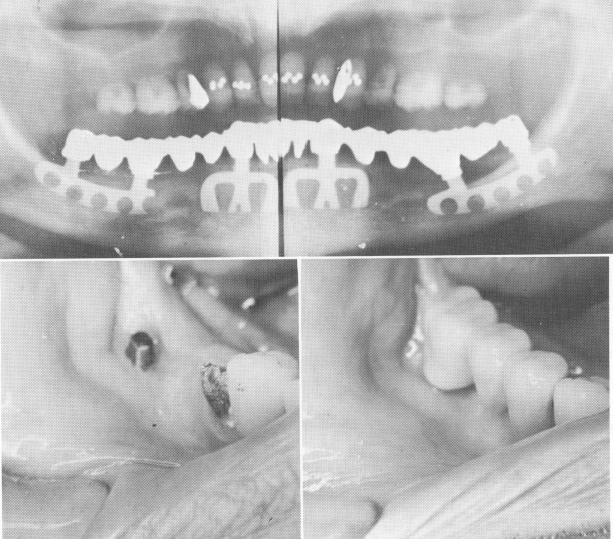

Fig. 11-16. Blades for extremely resorbed mandibles. A, The groove is made buccally to the mandibular canal. B, The right posterior implant in this case was set buccally to the mandibular canal. C, Here a blade was set near the external oblique ridge to avoid perforating the mandibular canal. D, The finished case, a unilateral partial fixed porcelain-baked-to-metal prosthesis.

1 Groove made buccally to the mandibular canal for bladevent placement

2 Right posterior implant set buccally to the mandibular canal